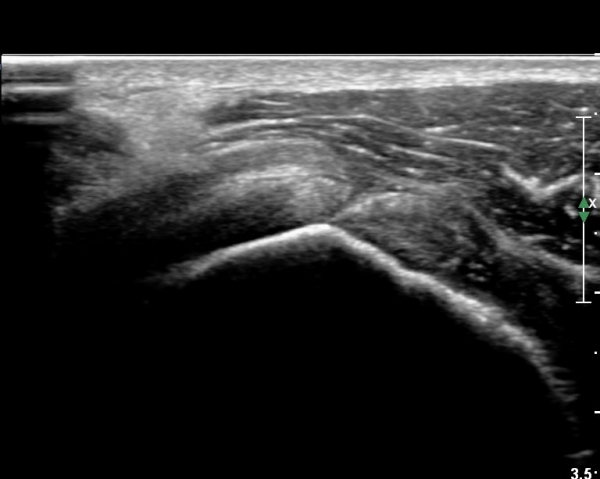

º¸¿© °ß°©ÇÏ±Ù°Ç ÆÄ¿­ÀÌ ÃßÁ¤µÈ´Ù(»çÁø 1). ŽÃËÀÚ¸¦ ¾à°£ ¾Æ·¡·Î À̵¿ÇÑ ÈÄ

ÆÈÀ» ¿ÜȸÀüÇϸ鼭 °üÂûÇÏ´Ï °ß°©ÇÏ±Ù°Ç ÆÄ¿­ÀÌ ¶Ñ·ÈÇÔ(»çÁø 2, 3).